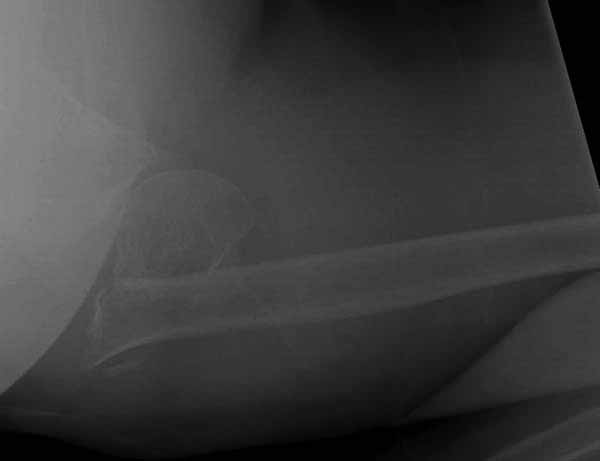

Уважаемы коллеги! Прошу помочь определиться с тактикой лечения пациентки. В феврале в отделение поступила пациентка с оскольчатым переломо-вывихом головки плечевой кости. Выполнена операция -остеосинтез блокируемой пластиной. Костная пластика не производилась. На контрольных рентгенограммах остается сублюксация головки и смещение большого бугорка. Интраоперационно бугорок подшивался с помощью лавсановых нитей. Послеоперационно: ношение косыночной повязки и пассивные движения в плечевом суставе в течение 2,5-х месяцев без особенностей. Через 2,5 месяца при попытке выполнения пассивно-активных движений произошел передний вывих плечевой кости.Вся реабилитация производилась по месту жительства. Таким образом существование вывиха в течение 1 месяца. Боли не беспокоят. Нейрососудистых нарушений в конечности нет. Что вы можете посоветовать: пластику, эндопротез, артродез? Заранее спасибо.

Спасибо вам, Олег, за ответ. То что нет болевого синдрома в покое тоже меня удивляет. Скорее всего придется сделать пластику ( с лавсановой лентой). К сожалению, прошло много времени и фрагмент большого бугорка скорее всего выделить не удастся. Функция ротаторов тоже мне видится утраченной. Будем думать.

Немного причин, приводящих к вывихам после фиксации переломов проксимального плеча. В результате несоответствия суставной поверхности лопатки и головки плеча из-за потери кости по задней поверхности головки плеча или в задней половине суставной впадины. Или в результате отсутствия мягкотканого покрытия, к которому можно отнести разрывы манжетки или суставной капсулы. А также когда повреждается нерв.

Для адекватного лечения необходимо знать состояние костного компонента - нужно КТ с артрографией что поможет частично оценить состояние сухожилий и лабриум. Уже по снимку можно сказать что существует большой костный дефект в задне-наружном сегменте.